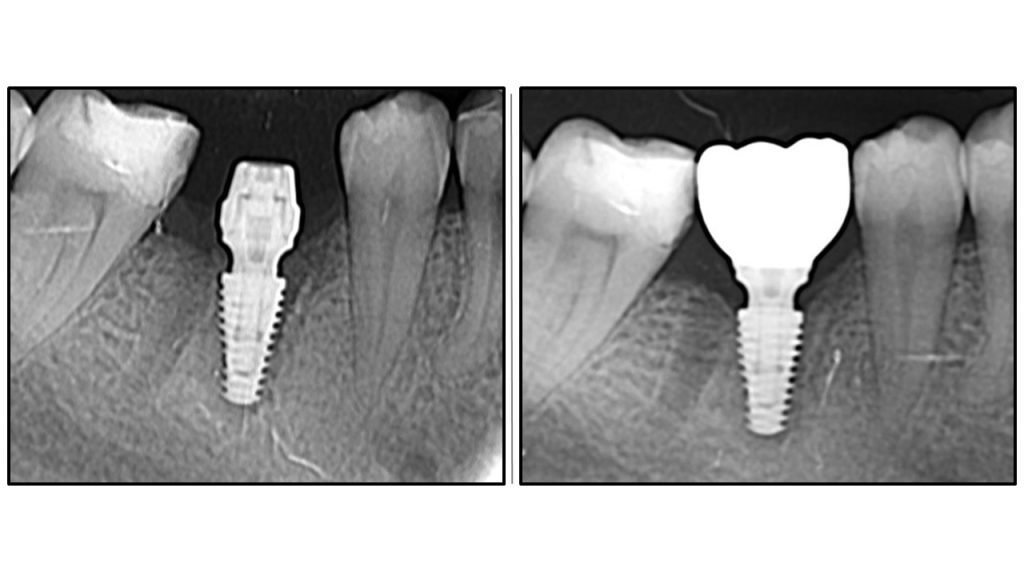

Радиографска анализа: стабилност костине крошне